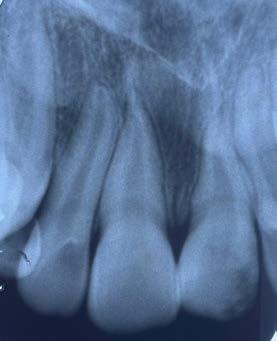

Figura 1. Radiografía inicial de la paciente. Se observa edentulismo total superior, a excepción del molar del primer cuadrante, indicado para exodoncia. En la mandíbula se aprecia pérdida ósea horizontal generalizada secundaria a la evolución de la enfermedad periodontal.

En la radiografía inicial (Figura 1) se observa la pieza 17 con pérdida ósea significativa, así como una reabsorción ósea homogénea a lo largo de todo el arco superior. En la arcada inferior se aprecia pérdida ósea horizontal generalizada y defectos localizados, como una lesión en cuña en la pieza 46. Ante esta situación, se decide realizar la exodoncia del molar remanente del

En el examen radiográfico se observó una zona radiolúcida a nivel coronario del O.D. 2.1 en los tercios antes referidos; asimismo, se identificó una porción radicular disminuida en comparación con el O.D. 1.1, así como curvatura radicular (Figura 3).